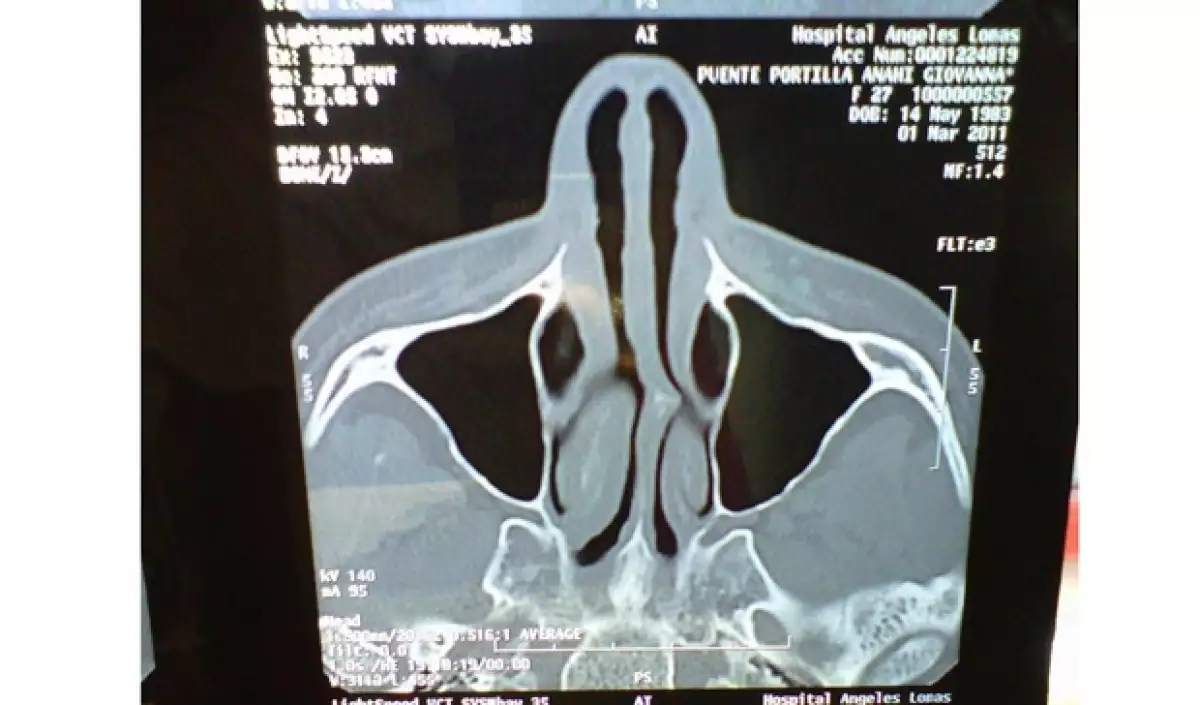

"Hace un par de días, se realizaron unos estudios médicos en los que a través de una tomografía se descubrió que el oxigeno que naturalmente debe de llegar al cerebro, estaba bloqueado en un gran porcentaje debido a un tabique desviado en la nariz causado por un golpe a temprana edad.

Por supuesto, durante el paso de las horas y los días, la intérprete de "Alérgico" se mostró un poco molesta por la prensa amarillista, así como por las personas que la atacaron inventando varias cosas de su entrada al hospital, por lo que subió la tomografía que le realizaron para desmentir todo lo que se había dicho de ella.

"Una vez más la tomografía de mi nariz... eso era lo q tenía" y remató escribiendo: "Ese fue un regalito para los malvibrosos q seguro ni le entienden pero eeequiiisquetevalga! Sean felices mundo" (sic).